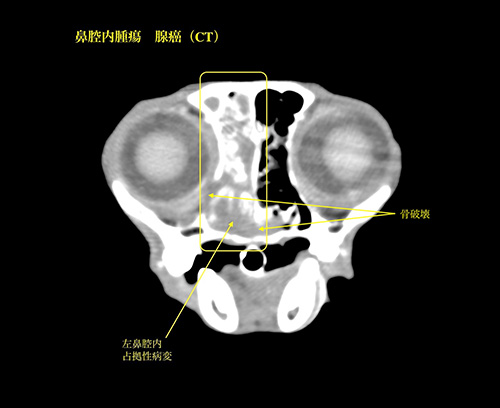

鼻腔内腫瘍(腺癌)